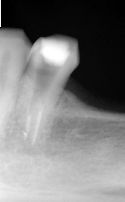

Ząb - lewa dolna czwórka. Bolał po leczeniu kanałowym. Podjęto decyzję o leczeniu pod mikroskopem. Odnaleziono i udrożniono drugi kanał korzeniowy. Dolegliwości ustąpiły.